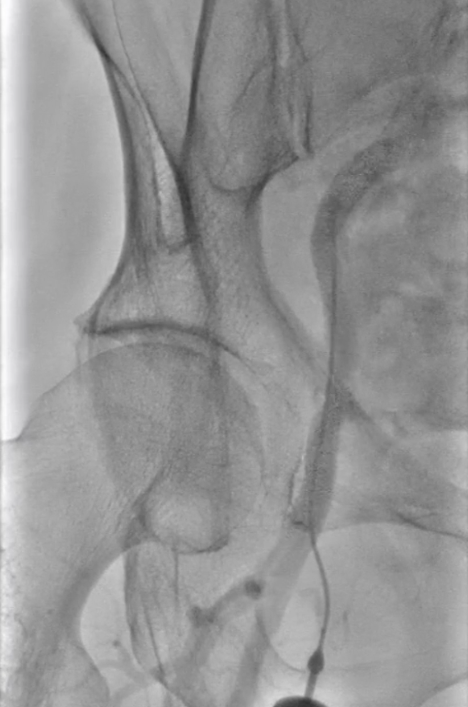

主动脉弓造影确认分型为Ⅰ型弓,为后续操作提供解剖参考

★ 病变评估

左侧颈总动脉造影:明确左侧颈内动脉闭塞,侧支循环通过颈外动脉部分供应颅内血流;

右侧颈总动脉造影(正位、汤氏位、侧位):明确右侧颈内动脉重度狭窄,病变远端直径5mm、近端直径8mm,长度约30mm,远端锚定区条件理想。